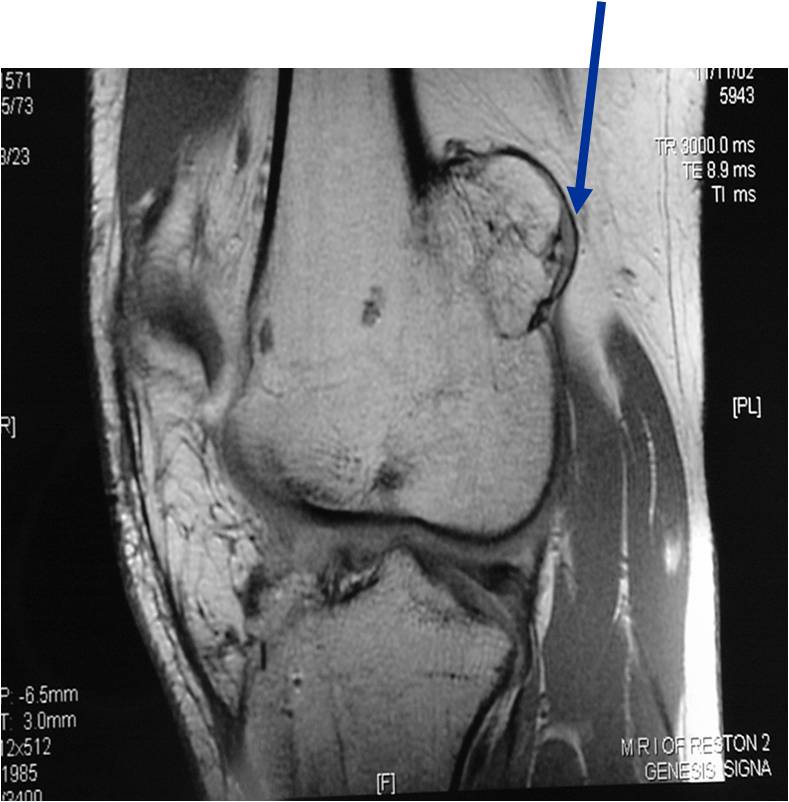

Osteochondroma Vs. Secondary Chondrosarcoma

The cartilaginous cap deserves the most attention when differentiating a benign osteochondroma from a secondary chondrosarcoma that arose from a pre-existing osteochondroma

In adults, the cartilaginous cap regresses and becomes thin due to enchondral ossificastion of the majority of the cap.

Malignant transformation is suggested by:

- Cartilaginous cap thickness greater than 2cm

- Cortical destruction

- Backgrowth of the cartilaginous cap into the stalk or medullary canal

- Lysis of calcifications in cap

- Best test for evaluating thickness of cap and surrounding bursa

MRI: Secondary Chondrosarcoma of Proximal Femur: Thick Cartilage Cap (>2cm)